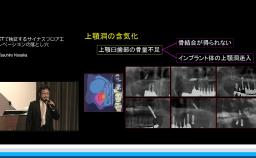

サイナスフロアエレベーションの長期経過症例から学ぶ本講演では、サイナスフロアエレベーションに関するトラブル、そのトラブルを防ぐための診査・診断・意思決定、四半世紀の臨床を通じて臨床例・長期経過症例から学ぶこと、そしてサイナスフロアエレベーション部位に埋入されたインプラントの臨床成績について報告があった。まずサイナスフロアエレベーションにおけるトラブルを防ぐための診査・診断として上顎臼歯部の欠損状態と解剖学的形態を把握し、インプラント治療の適応となればその適切なアプローチの仕方を検討することが重要である。更には移植材料について、文献を通じてそれぞれの特徴や生存率に関して報告された。サイナスフロアエレベーションは正しい診断と適切な外科手技の元に行えば上顎臼歯部における骨造成を伴う方法として非常に確立された方法と考えられると結んでいる。

- サイナスフロアーエレベーションのトラブルを防ぐための診査診断